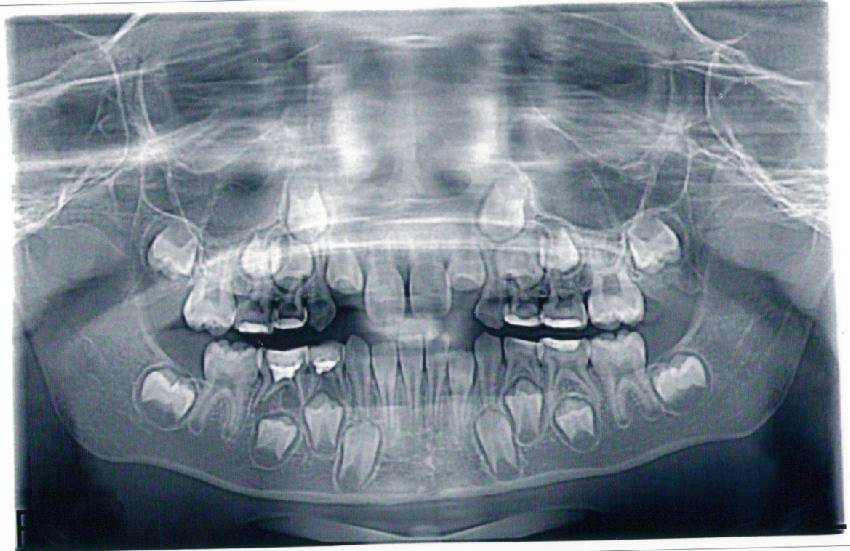

Медицинские Исследования: Кортикальная Пластинка на ОПТГ